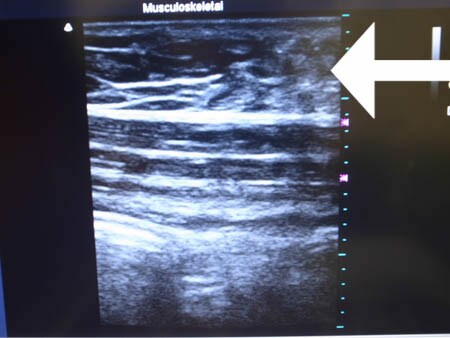

同様に下腹部 ↓ ↓ ↓

↓ ↓ ↓

いかがでしょうか?

外見上では判断できない

体内の皮下脂肪層を

3Dタッチビューでしっかりと見て

皮下脂肪の取り残しがないか?

皮下脂肪の取りむらはないか?

チェックすることは

非常に大切だと思いますし

また手術が終了した時点で

確実な結果を患者様にお約束でき

さらに患者様にもこの画像を見ていただけば

非常に満足度の高い手術になります。

今回も患者様は術中にこの画像を見て

非常に満足されていました!